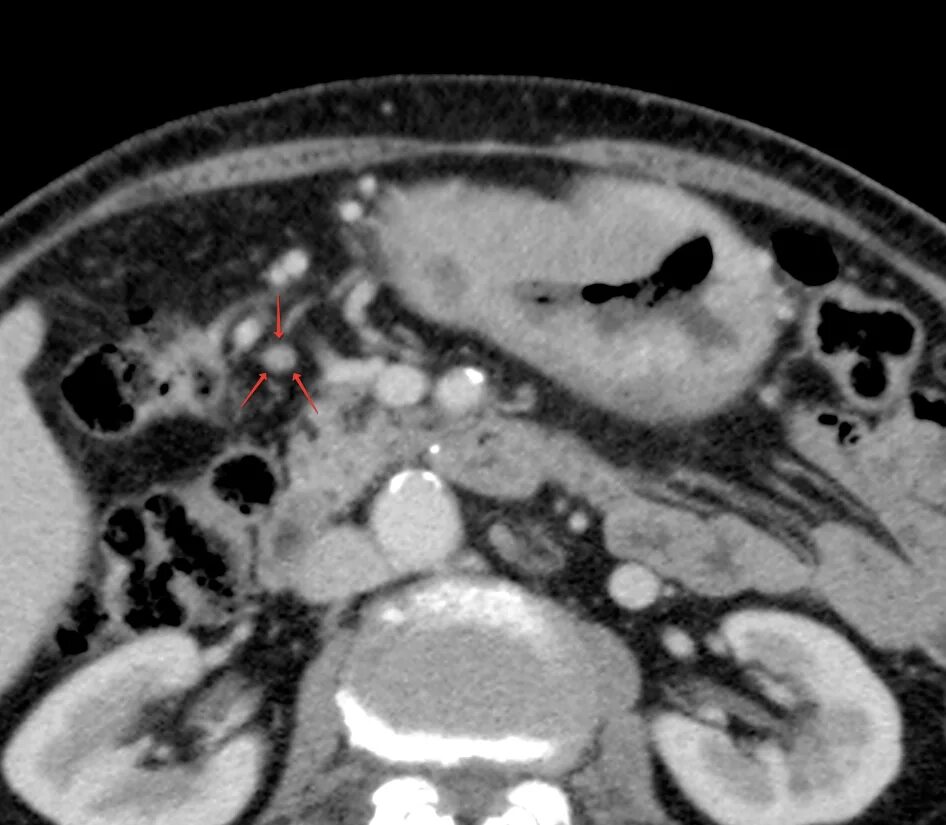

Язва желудка кт